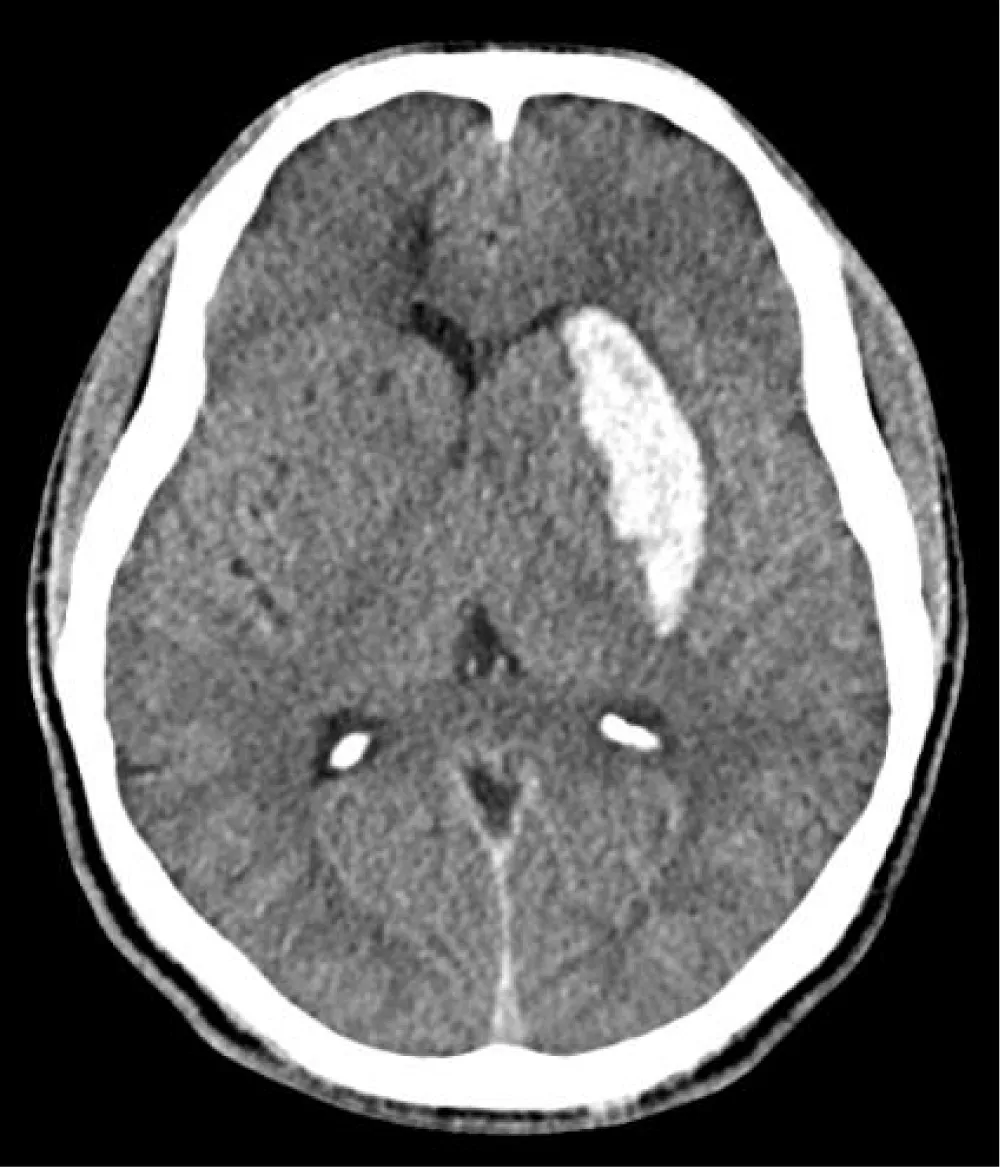

He was airlifted to the closest hospital within 24 hours. On arrival, he had a Glasgow Coma Scale of 6/15 (E=2; M=3; V=1), a dense Right-sided hemiparesis, and vomiting. His blood pressure was 200/123 mmHg which was controlled initially with Intravenous labetalol and doxazocin. CT head (Figure 1) showed an intraparenchymal bleed involving the basal ganglia (on the left, particularly the putamen, head of the caudate, and the anterior limb of the internal capsule. The patient was intubated and ventilated. A CT angiogram did not demonstrate any vascular abnormalities. After consultation with the regional neurosurgical center, there was no surgical intervention.

Figure 1: CT Head.